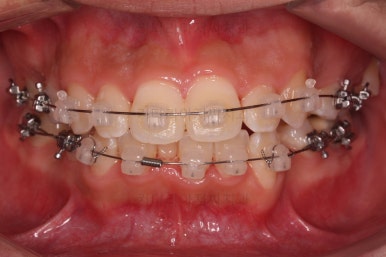

초진 시 입안의 모습입니다.

앞니가 많이 삐뚤고, 송곳니가 부각되어 덧니처럼 보이네요.

장치를 처음 부착한 모습입니다.

이번 환자분이 선택하신 장치는 데이몬 클리어라고 하는 자가결찰 세라믹 장치인데요.

흔히들 아시는 클리피씨 장치 등등에 비해 현존하는 브라켓 중에 가장 심미적인 장치입니다.